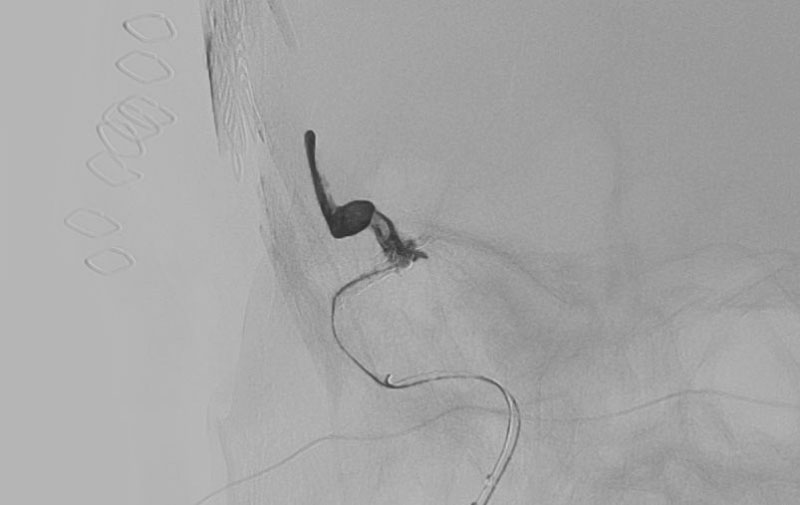

'25年11月

くも膜下出血

右内頚動脈後交通動脈

分岐部動脈瘤破裂

60代

救急外来

No.1593 手術前

No.1593 手術中

No.1593 手術後